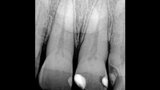

Jednoduchá souhra odstínů k vytvoření opticky harmonické výplně